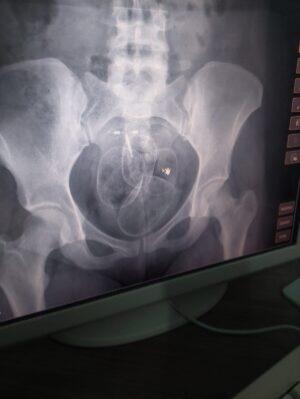

De acordo com os policiais, 250 de maconha e 60 gramas de cocaína foram retirados da parte íntima de uma das mulheres que tentava a visita a um dos presidiários pela manhã.

De acordo com as imagens obidas pela reportagem, as drogas estavam dentro de papelotes que foram inseridos no ânus da mulher. Maior apreensão realizada na unidade dessa maneira.

Já no turno da arde, uma jovem de 25 anos foi flagrada com papelotes de cocaína e maconha também no ânus, mas em menor quantidade.

O histórico da ocorrência conta que, durante o procedimento de revista corporal, foram visualizados objetos suspeitos pelo detector e as mulheres foram conduzida à Delegacia de Polícia onde devem responder por tráfico de drogas.